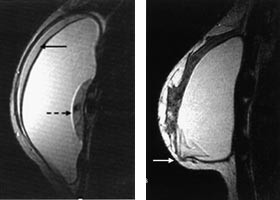

T2-vektede bilder i aksial- og sagittalplan gir god informasjon om silikonskallets integritet og differensierer godt mellom silikongel (høyt signal) og brystkjertelvev (lavt signal) (fig 5a ). Imidlertid vil subkutant fettvev og silikongel ofte ha relativt lik signalintensitet. Finner man tegn til implantatruptur på T2-vektede bilder, bør man derfor supplere med bildesekvenser som skiller godt mellom fettvev og silikon for å kunne påvise mulige silikonlokulamenter i fettvevet. Et eksempel på en slik sekvens er en ”inversion recovery” med kort T1 (STIR)-sekvens (fig 5b).

En intakt enkeltlumen silikonprotese er oftest oval med jevn overflate. Silikonskallet er signalfattig på alle typer bildesekvenser. Skallet er som regel vanskelig å skille fra den fibrøse bindevevskapselen som dannes rundt implantatet. Radiære innfoldinger av proteseskallet sees hyppig og må ikke forveksles med ruptur (fig 6). Innfoldingene kan være markerte, men kan alltid følges ut til protesens overflate. Reaktiv væske rundt implantatet sees ofte og er ikke et tegn på ruptur. Er væskemengden uttalt, kan et enkeltlumen silikonimplantat feiltolkes som et dobbeltlumenimplantat med et ytre saltvannslumen. I dobbeltlumenimplantater (fig 7a) vil ofte det indre skallet som skiller de to lumen vise uttalte innfoldinger, uten at dette er tegn på ruptur. Noen ganger kan implantatet herniere ut gjennom små defekter i den fibrøse kapselen som omgir protesen (fig 7b). Dette kan gi palpable resistenser og oppfattes klinisk som en brysttumor.

Ved ruptur av silikonskallet vil silikongel lekke ut mellom skallet og den omgivende fibrøse kapsel. Skallet vil fremstå som signalfattige streker inne silikongelen. Ved en liten ruptur vil skallet ligge parallelt med den fibrøse kapselen (fig 8a), men ved mer uttalte rupturer folder skallet seg sammen og ligger som slyngede tråder (fig 8b). Ved ruptur av saltvannsimplantater skjer en rask reduksjon i implantatets størrelse fordi saltvannet absorberes lett. Ved ekstrakapsulære rupturer er det en defekt både i silikonskallet og i omgivende fibrøs kapsel. I tillegg til funn som ved intrakapsulær ruptur sees større eller mindre silikonlokulamenter utenfor kapselen.